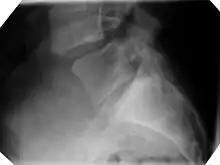

X-ray of the lateral lumbar spine with a grade III anterolisthesis at the L5-S1 level.